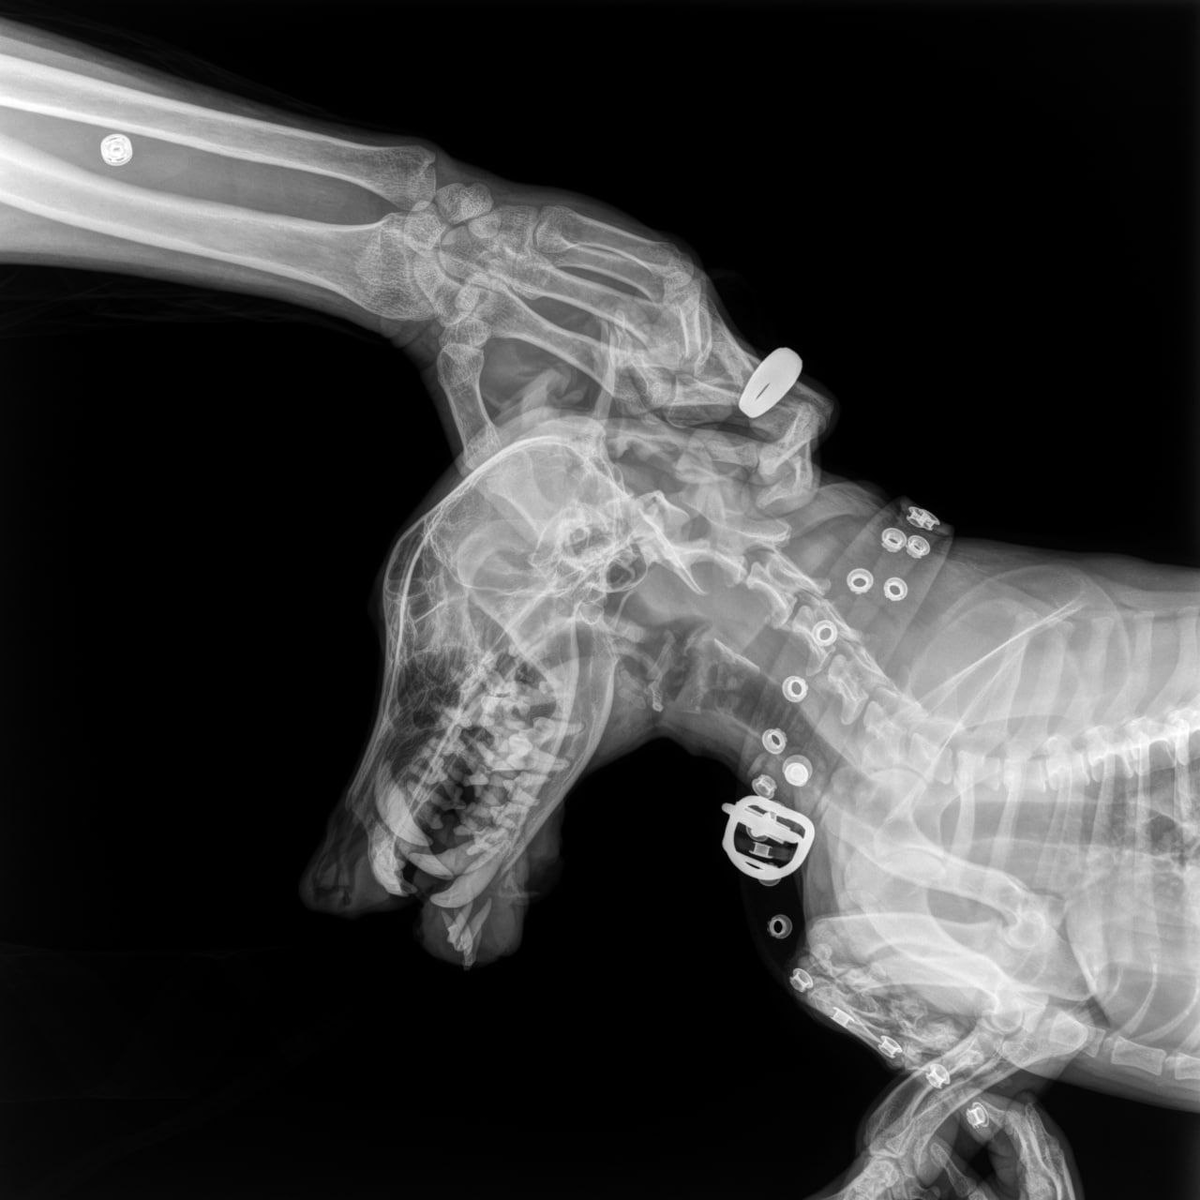

Рентген Сэма

Я не пристраивала Сэма, т к он страшная кусючка. Вот сколько он живёт, я всегда с ним осторожна, да гладится, да слушает, но тут же укусит. Сейчас он на стационаре в Донецке, вчера его отвёз водитель, т.к. на нижней челюсти образовалась шишка, я думала укусили, но нет шишка росла и по рентгену там уже задета кость.

Похоже на онкологию, и я очень расстроена, он хоть и кусается, но я люблю его.